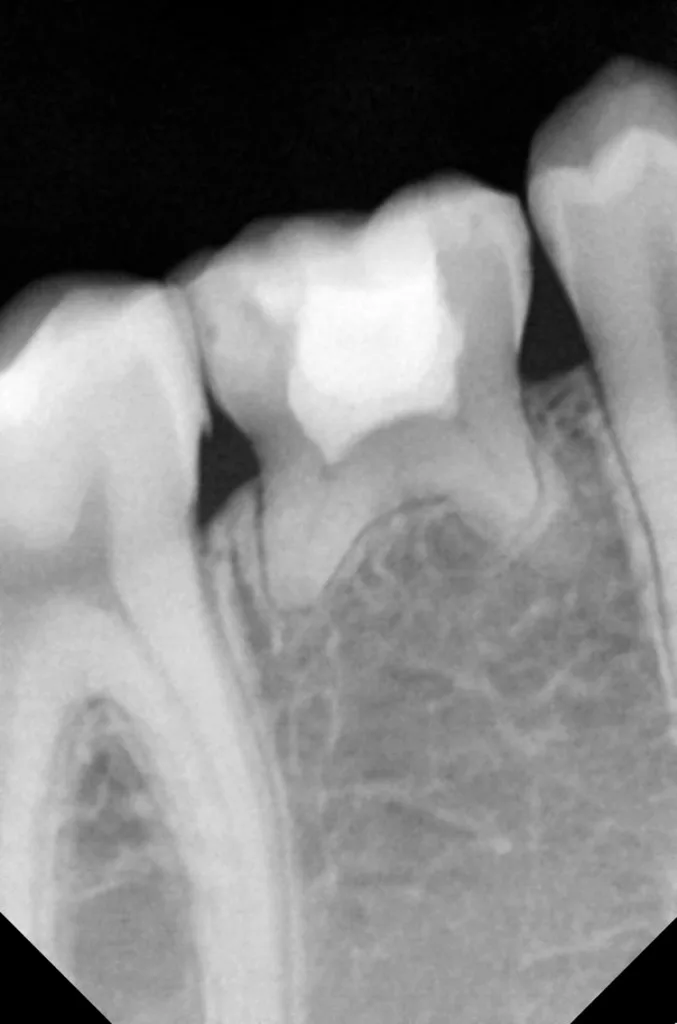

Auf einer die Untersuchung ergänzenden Röntgenaufnahme wurden die Nichtanlage des 2. Prämolaren und die Wurzelresorption mit einem periapikalen Prozess festgestellt (Abb. 1). Weil es keine Anzeichen einer Ankylose oder einer Infraokklusion gab, welche das Wachstum des Alveolarfortsatzes stören könnten, wurde nach eingehender Aufklärung über die Therapieoptionen und die Prognose gemeinsam mit den Eltern beschlossen, einen Behandlungsversuch zum Erhalt dieses Zahnes zu starten.